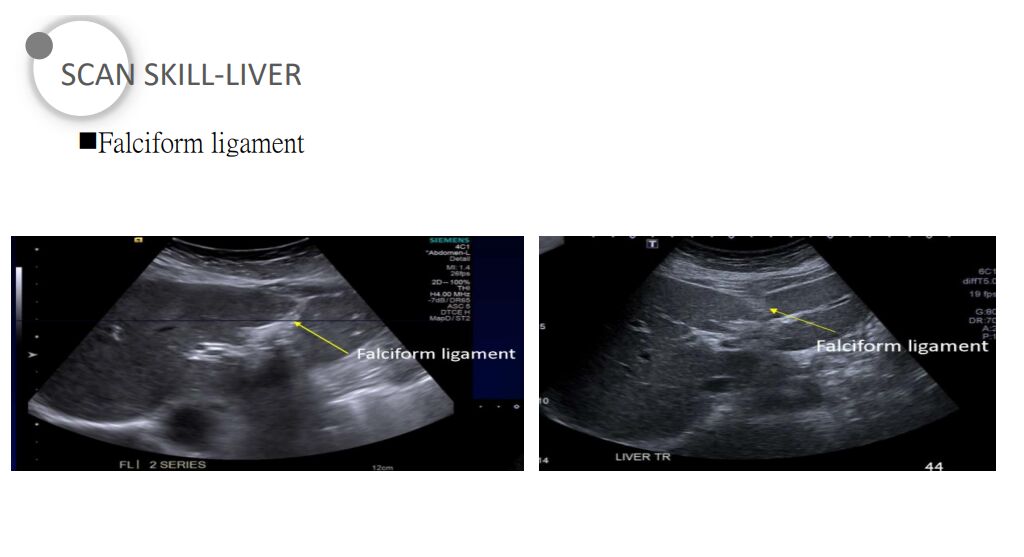

61.肝臟超音波橫向掃描時,在外側節段(lateral segment, L)與尾葉(caudate lobe, C)之間有 一高回音裂隙(fissure, F),如下圖箭號處。此高回音裂隙與下列何者最有關係?

尾葉的左邊邊界是靜脈韌帶(ligamentum venosus),因此這題所指的高回音裂隙就是靜脈韌帶

註:靜脈韌帶是胎兒時期的靜脈導管 (ductus venosus)閉鎖遺跡

(C) 圓韌帶(ligamentum teres)在方葉 (quadrate lobe) 的左邊邊界

註:圓韌帶是胎兒時期的左臍靜脈 (left umbilical vein) 閉鎖遺跡

(D) 鎌狀韌帶(falciform ligament)區分左右兩葉